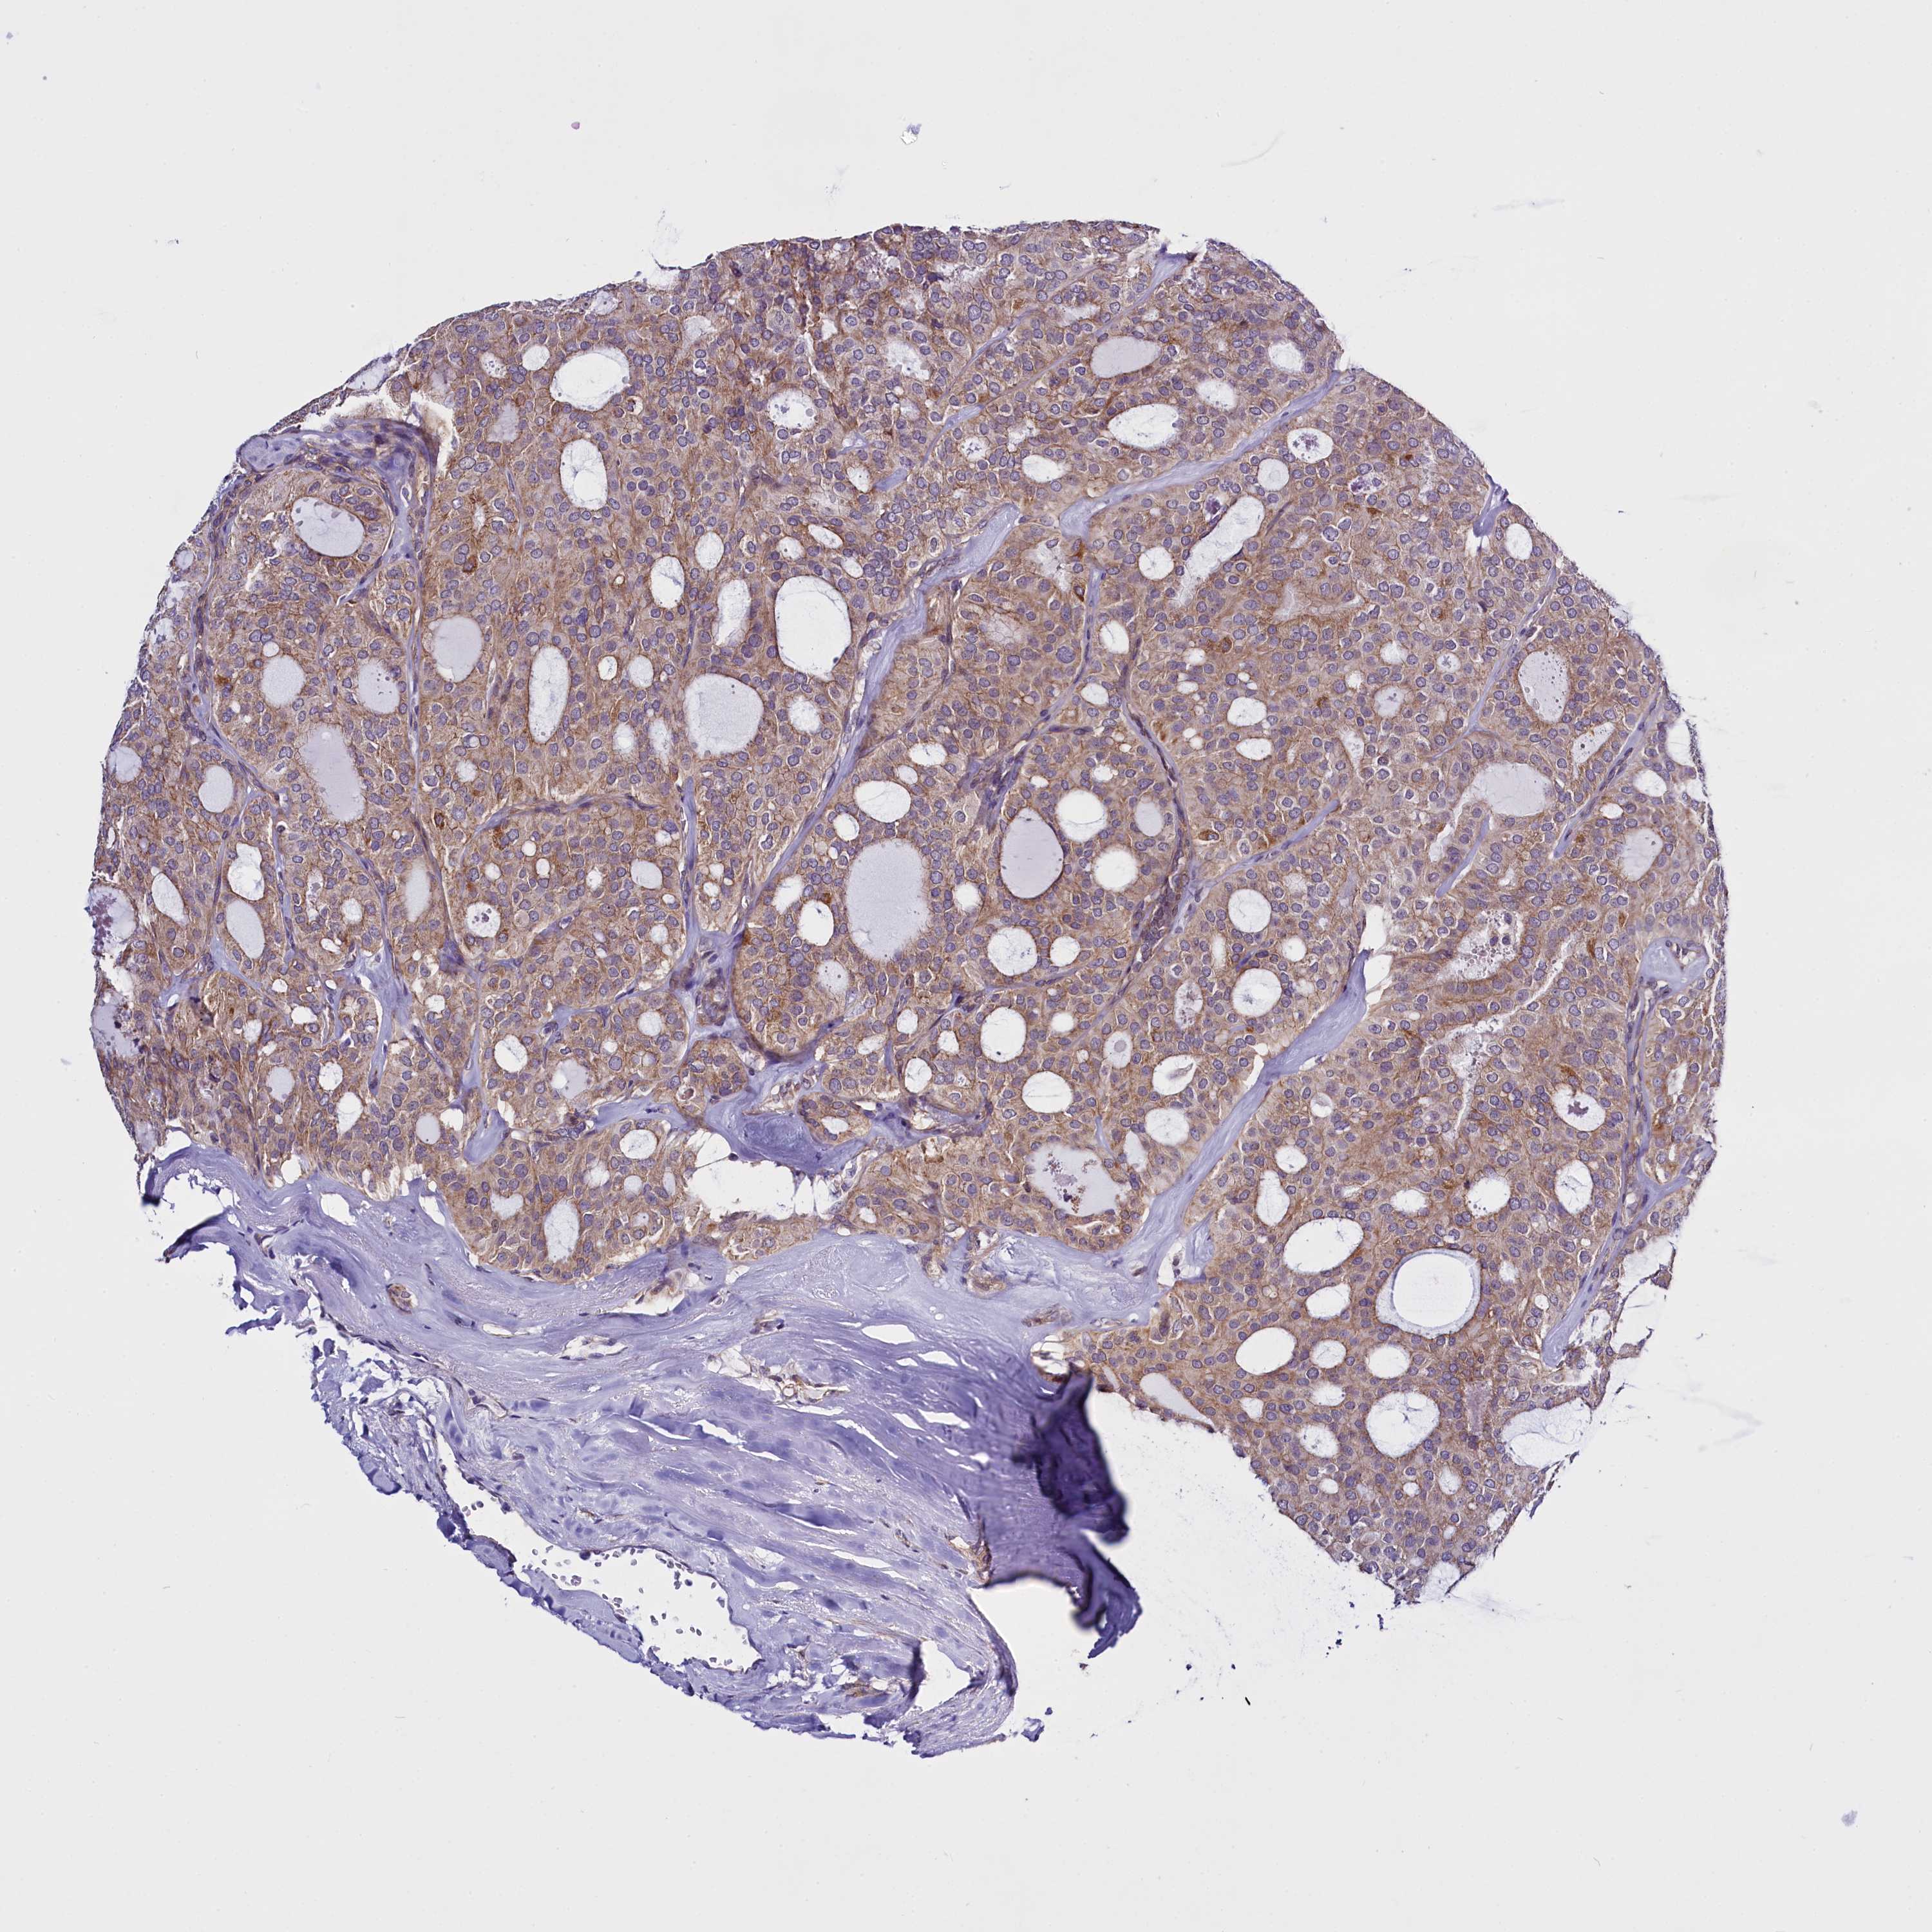

THYROID CANCER - Protein expressioni

A mouse-over function shows sample information and annotation data. Click on an image to view it in a full screen mode. Samples can be filtered based on level of antibody staining by selecting one or several of the following categories: high, medium, low and not detected. The assay and annotation is described here.

Note that samples used for immunohistochemistry by the Human Protein Atlas do not correspond to samples in the TCGA dataset.

Antibody stainingi

Antibody staining in the annotated cell types in the current human tissue is reported as not detected, low, medium, or high, based on conventional immunohistochemistry profiling in selected tissues. This score is based on the combination of the staining intensity and fraction of stained cells.

Each image is clickable and will lead to virtual microscopy that enables deeper exploration of all samples and also displays staining intensity scores, fraction scores and subcellular localization as well as patient and tissue information for each sample.

Antibody HPA041412

Antibody HPA056006

Staining

High

Medium

Low

Not detected

Intensity

Strong

Moderate

Weak

Negative

Quantity

>75%

75%-25%

<25%

None

Location

Nuclear

Cytoplasmic/membranous

Cytoplasmic/membranous,nuclear

Papillary adenocarcinoma, NOS

Follicular adenoma carcinoma, NOS